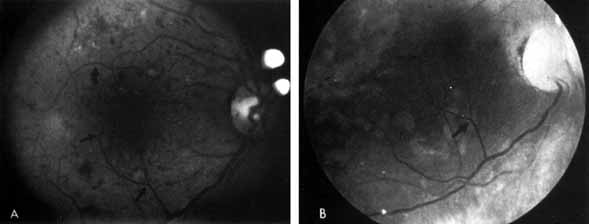

EARLY NONPROLIFERATIVE DIABETIC RETINOPATHY

Although microaneurysms are the first ophthalmoscopically detectable change in diabetic retinopathy, the earliest abnormalities seen histopathologically are thickening of the capillary basement membrane1,2 and pericyte dropout.3,4 Pericytes are mesothelial cells that surround and support the retinal capillary endothelial cells. Normally there is one pericyte per endothelial cell. In people with diabetes, however, the pericytes die off and are decreased in number (Fig. 1). Their absence weakens the capillaries and permits thin-walled dilatations, called microaneurysms, to develop. Later, endothelial cells proliferate and lay down layers of basement membrane material. Fibrin may accumulate within the microaneurysm along with erythrocytes, and the lumen of the microaneurysm may become occluded (Fig. 2). Initially, most microaneurysms are on the venous side of the capillaries, but later they are seen on the arterial side as well. Clinically, they appear as small red dots (Fig. 3). Despite the multiple layers of basement membrane, microaneurysms are permeable to water and large molecules, allowing the transudation of fluid and lipid into the retina.

Fig. 3 A. Diabetic retinopathy with multiple microaneurysms, dot hemorrhages, and early neovascularization of the optic disc (NVD). A small blot hemorrhage is seen inferiorly. B. Continued. Midphase of the fluorescein angiogram. Patent microaneurysms are seen as hyperfluorescent dots. Note that most microaneurysms cannot be seen ophthalmoscopically. There is some enlargement of the foveal avascular zone because of some occluded capillaries. Temporally there is a larger zone of capillary nonperfusion. The NVD is beginning to leak. C. Late phase of the fluorescein angiogram showing diffuse leakage of fluorescein into the macula.

It is often difficult to distinguish a small dot hemorrhage from a microaneurysm by ophthalmoscopy alone. On fluorescein angiography patent microaneurysms will fill with dye quickly and then leak,5 unlike a small dot hemorrhage that will block fluorescence (see Fig. 3). However, angiography cannot distinguish a hemorrhage from a microaneurysm filled with clotted blood. Because fluorescein passes easily though them, we usually see many more microaneurysms on fluorescein angiography than are apparent on examination.6

When the wall of a capillary or microaneurysm is thin, it may rupture, giving rise to an intraretinal hemorrhage. If the hemorrhage is deep (i.e., in the inner nuclear layer or outer plexiform layer), it usually has a round or oval shape (“dot or blot”) (see Fig. 3). Superficial (nerve fiber layer) hemorrhages, on the other hand, become flame- or splinter-shaped indistinguishable from that seen in hypertensive retinopathy. Although people with diabetes with normal blood pressure may have multiple splinter hemorrhages, they should nevertheless have their blood pressure checked because a frequent complication of diabetes is systemic hypertension.